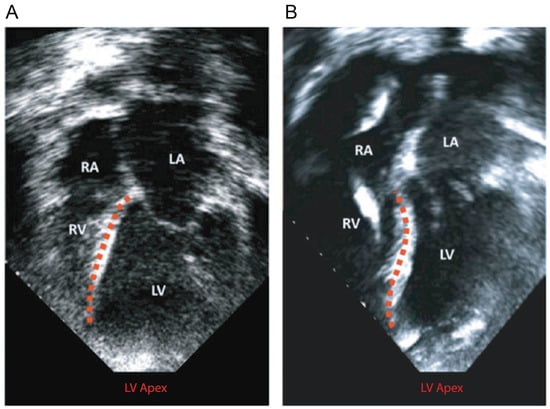

- Sack, K.L.; Aliotta, E.; Choy, J.S.; Ennis, D.B.; Davies, N.H.; Franz, T.; Kassab, G.S.; Guccione, J.M. Intra-Myocardial Alginate Hydrogel Injection Acts as a Left Ventricular Mid-Wall Constraint in Swine. Acta Biomater. 2020, 111, 170–180. [Google Scholar] [CrossRef]